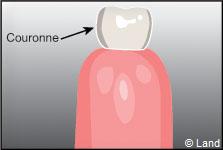

La dent est composée d’une couronne et d’une ou plusieurs racines incluses dans l’os alvéolaire.

La partie la plus externe de la couronne, l’émail, est composée principalement d’éléments minéraux, ce qui lui confère dureté et solidité.